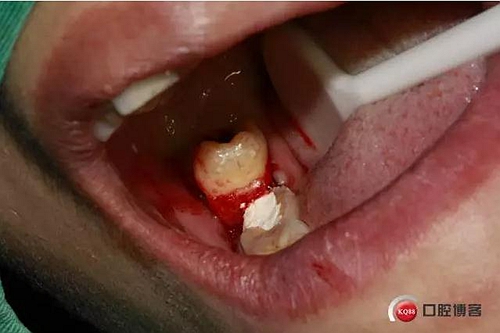

口內(nèi)照片,48遠(yuǎn)中三分之一覆蓋部分牙齦。

48牙冠比較大。